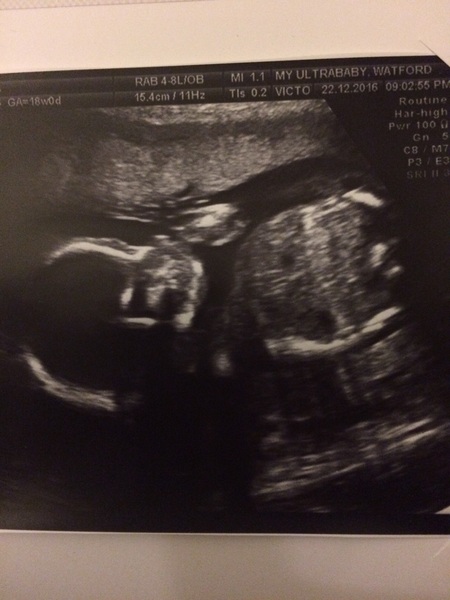

Yay! Congrats shoni and jonsnow Smile It really is the best Xmas pressie ever isn't it! Ours was sucking it's thumb. So amazing.